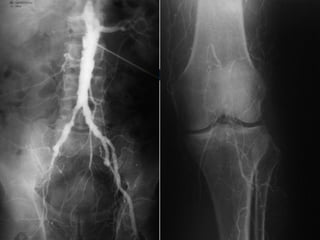

O PÉ DIABÉTICO E SUAS ESPECIFICIDADES   VASCULOPATIA DIABÉTICA   ALTERAÇÕES DA MICROCIRCULAÇÃO CUTÂNEA ATEROSCLEROSE DAS EXTREMIDADES INFERIORES  (calcificações parietais e predomínio de doença femoro popliteia e distal) FUNÇÃO IMUNE CITOMEDIADA ESTÁ ALTERADA  -  MAIOR RISCO DE COLONIZAÇÃO E INFECÇÃO BACTERIANA

ISQUÉMIA CRÍTICA TRATAMENTO - Revascularização Cirurgia convencional Cirurgia endovascular - Proximal - Distal - Multisegmentar

O PÉ DIABÉTICOE SUAS ESPECIFICIDADES VASCULOPATIA DIABÉTICA ALTERAÇÕES DA MICROCIRCULAÇÃO CUTÂNEA ATEROSCLEROSE DAS EXTREMIDADES INFERIORES (calcificações parietais e predomínio de doença femoro popliteia e distal) FUNÇÃO IMUNE CITOMEDIADA ESTÁ ALTERADA - MAIOR RISCO DE COLONIZAÇÃO E INFECÇÃO BACTERIANA

ISQUÉMIA CRÍTICA TRATAMENTO- Revascularização Cirurgia convencional Cirurgia endovascular - Proximal - Distal - Multisegmentar